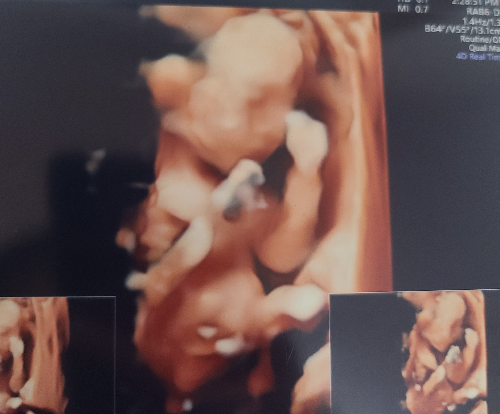

그 사이에 2배가 됐어 뿜뿜아. 완전히 아기 모습이네 이젠. 진짜 너무너무 귀여워. 290g이 이렇게 잘 보일 줄 몰랐는데.

임당 검사 통과! 노산에 뚱뚱이 엄마라서 걱정했는데 한 번에 통과했다 ㅎㅎ 그리고 지난번 걱정과 달리 뿜뿜이 위도 아주 잘 보여서 식도도 잘 자라고 있다고 했다. 지난번에 너무 쪼꼬미라서 안 보였나 봐. 입도 벌렸다 오므렸다 하면서 메롱도 하고 귀여웡~😜 초음파 사진을 봤는데 나를 닮은 것 같다. 아빠 유전가가 강할 줄 알았는데 오뚝한 코가 아빠코가 아니라 엄마 코처럼 생겼어. 얼굴은 둥글둥글한데 턱을 뾰족한 게 나를 닮은 거 같다. 나와봐야 알겠지만 진짜 너무 귀엽다.